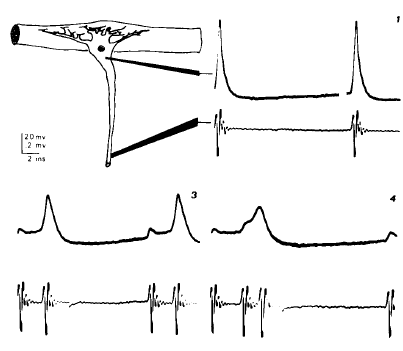

Mammalian peripheral axons respond to local disruption of their myelin sheath with membrane changes which support continuous conduction of the impulse through the affected region. We report here that sites of demyelination may become foci of spontaneous impulse initiation. Such sites may also generate ectopic discharges upon slow mechanical distortion. Finally, conduction of an impulse train through a demyelinated region may set off an ectopic afterdischarge that may last many seconds. Rhythmic ectopic firing in dysmyelinated but conducting axons is very similar to that observed in regenerating axons and nerve-end neuromas. Although the latter have long been recognized as sources of pathophysiologic sensations, this is the first indication that neuralgias could arise following minor dysmyelination in peripheral nerves without substantial conduction deficits.